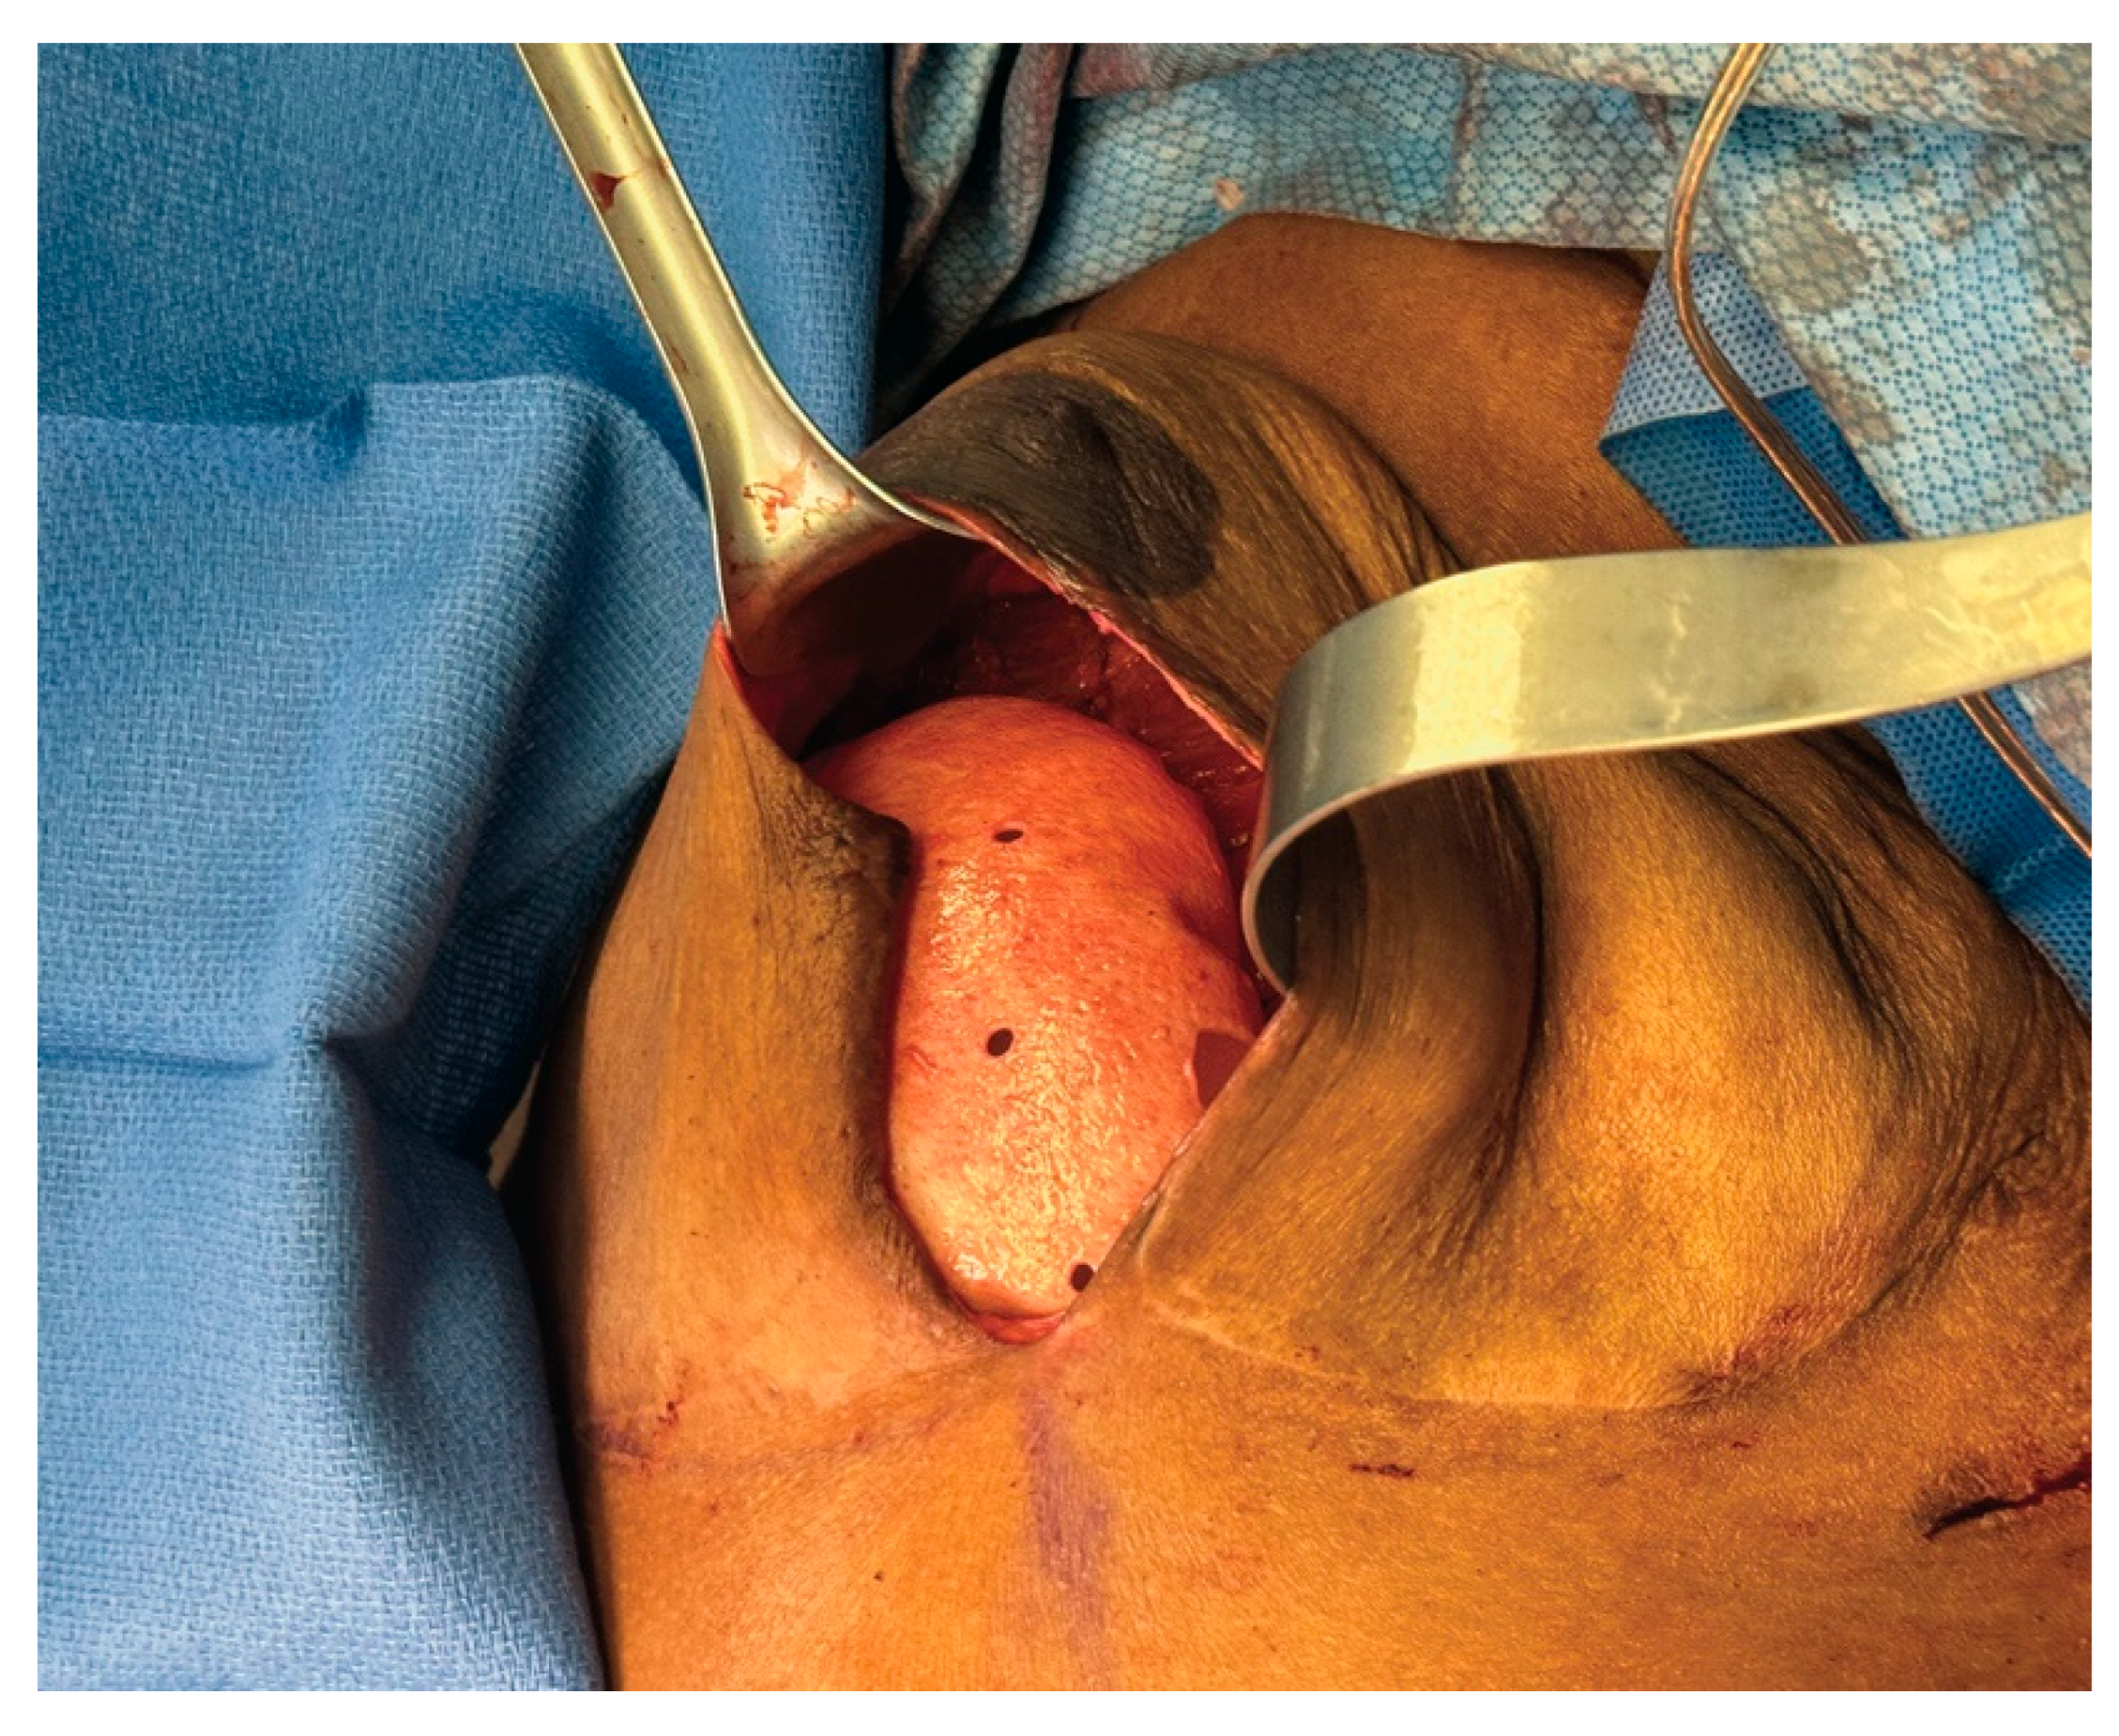

3.3. Case 1—HyFIL®

3.4. Operative Technique